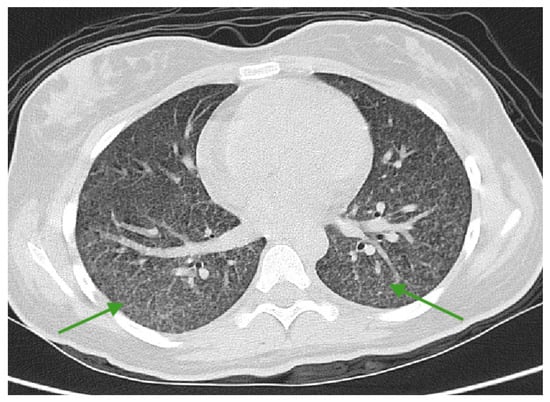

2. Case Report